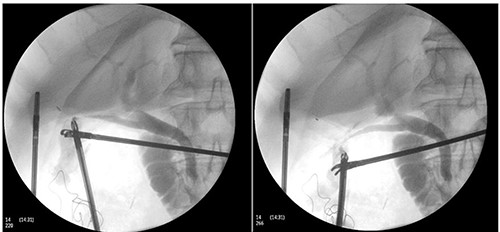

Perioperatively, retrograde dissection of gallbladder was performed due to gallbladder being thick, fibrotic, intrahepatic and access to Calot’s triangle was obscured by dense omental adhesions. Gallbladder was opened at Hartman’s pouch to perform an intraoperative cholangiogram safely; two bile-flowing tube structures were found at base of Hartman’s (Fig. 1). Intraoperative cholangiogram catheter was only able to be performed via one of the two ducts with no evidence of leak (Fig. 2). A Hepatobiliary Surgeon was consulted intraoperatively, the decision was to complete a subtotal cholecystectomy with the stump, containing both lumens, secured with Endoloop ties. 15F Blakes drain was placed at the gallbladder bed.

Intraoperative cholangiogram performed via one of two duct structures; double cystic duct not evident.

Subsequent review of preoperative imaging solved the mystery. Duplicated gallbladder with double cystic ducts was clearly evident on CT and magnetic resonance imaging (MRI) which were hidden in plain sight (Figs 4–7). CT cholangiogram (Fig. 3) was performed Day 1 post-operatively showing the double cystic duct with no evidence of bile leak. Rest of patient’s admission was uneventful and he was cleared for discharge on Day 5 post-operatively. Patient remains well and was back to his daily activities during his follow-up review.

CT cholangiogram performed Day 1 post cholecystectomy confirming double cystic ducts.